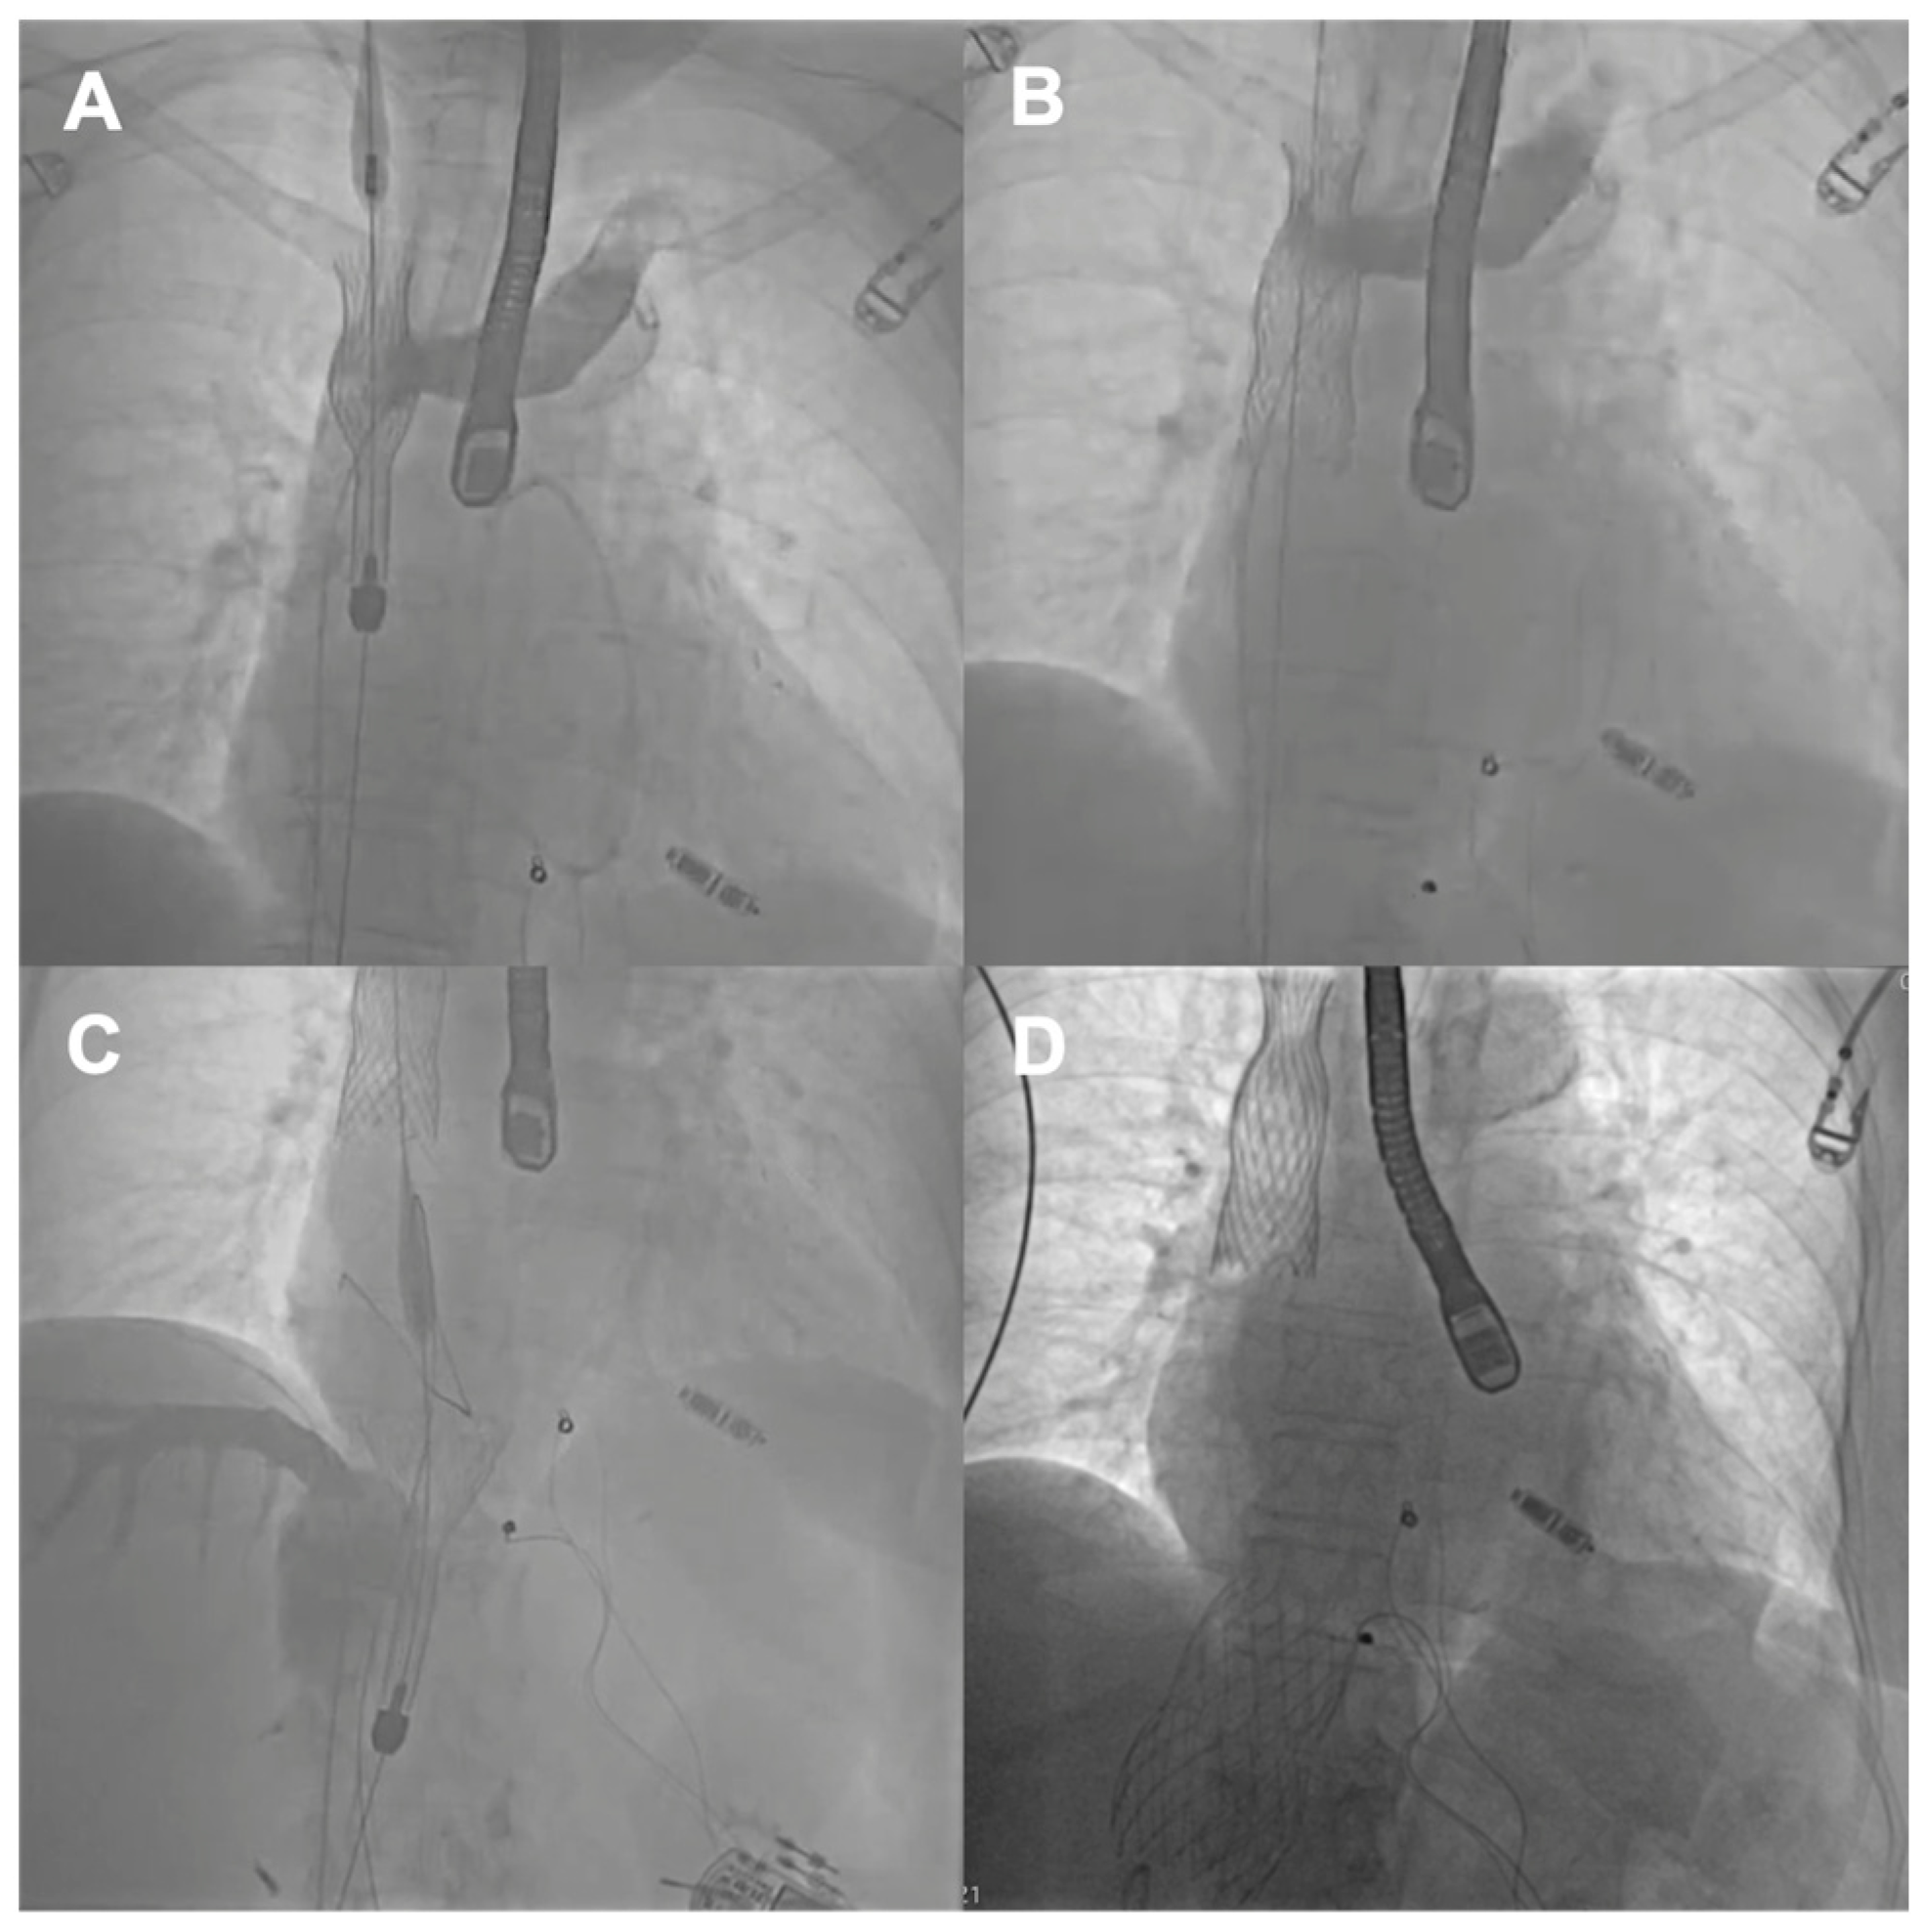

The first patient was a 77-year-old woman who had persistent heart failure symptoms (HF) in NYHA class III due to torrential regurgitation of the tricuspid bioprosthesis (CoreMatrix) that was implanted five years before. (Figure 1) The patient’s past medical history included a myocardial infarction 15 years before, coronary artery bypass grafting 15 years before, permanent atrial fibrillation, peripheral artery disease, type 2 diabetes, chronic kidney disease, and implantation of a leadless pacemaker. The patient suffered from recurrent exacerbations of HF that required hospitalization despite intensive diuretic treatment in the preceding year. Due to the very high predicted mortality risk (Table 1) and the history of two previous cardiac surgeries, the patient refused surgical treatment. Because the anatomy of the degenerated tricuspid bioprosthesis was not suitable for edge-to-edge treatment, the patient was offered the CAVI procedure. Valves of the TricValve system were implanted in the superior cava (SVC) and inferior vena cava (IVC), respectively, 21 mm and 41 mm. (Figure 2) The procedure was complicated, with access site bleeding requiring surgical intervention. The patient’s echocardiography, post their procedure, revealed a mild paravalvular leak in the IVC valve. One month after the procedure, the patient persisted in NYHA functional class II; however, during the following months, she was hospitalized due to exacerbation of their right ventricular failure. Eventually, the patient died 9 months after the procedure because of the progressive worsening of right ventricular dysfunction and multiorgan failure.

Figure 2. Consecutive steps of the TricValve procedure: (A) SVC stent positioning; (B) SVC stent implantation; (C) IVC stent positioning; (D) final angiographic result. SVC—superior vena cava; IVC—inferior vena cava.